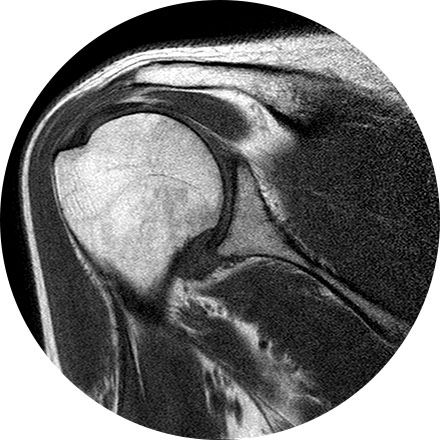

Arthrogram

An arthrogram is an X-ray exam of a joint, using a contrast agent and fluoroscopy (a live motion X-Ray). It is used to diagnose the cause of pain or restricted motion of a joint as well as injury to the components of the joint including, the tendons, soft tissues, ligaments, labrum, cartilage and bones. Often this procedure is used to image the shoulder and hip joints, and it is also used when investigating the knees, elbows, ankles and wrists. CT and MRI may also be used to gain additional images of the joint.